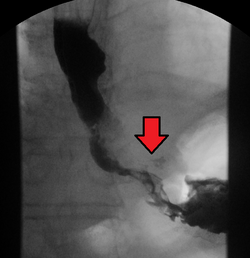

Although an occlusive tumor may be suspected on a barium swallow or barium meal, the diagnosis is best made with an examination using an endoscope. This involves the passing of a flexible tube with a light and camera down the esophagus and examining the wall, and is called an esophagogastroduodenoscopy. Biopsies taken of suspicious lesions are then examined histologically for signs of malignancy.

Additional testing is needed to assess how much the cancer has spread (see § Staging, below). Computed tomography (CT) of the chest, abdomen and pelvis can evaluate whether the cancer has spread to adjacent tissues or distant organs (especially liver and lymph nodes). The sensitivity of a CT scan is limited by its ability to detect masses (e.g. enlarged lymph nodes or involved organs) generally larger than 1 cm.[43][44] Positron emission tomography is also used to estimate the extent of the disease and is regarded as more precise than CT alone.[45] PET/MR as a novel modality has shown promising results in preoperative staging with fair feasibility and good correlation in comparison to PET/CT. It can enhance tissue differentiation with lowering the radiation dose to the patient.[46] Esophageal endoscopic ultrasound can provide staging information regarding the level of tumor invasion, and possible spread to regional lymph nodes.